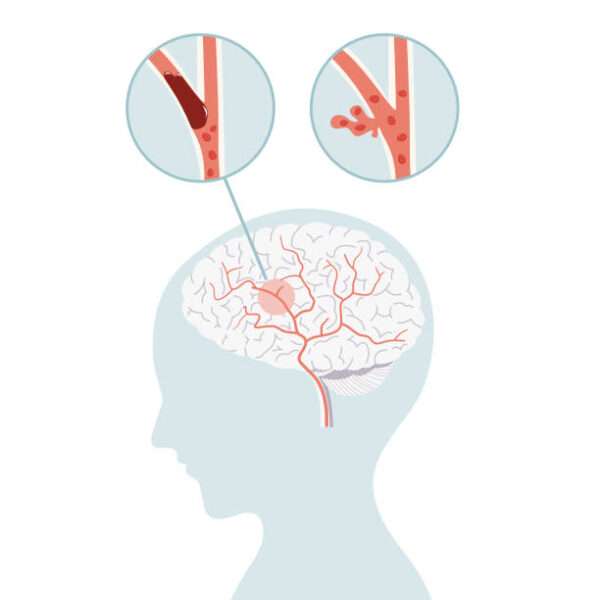

Enfermedad cerebrovascular oclusiva

La enfermedad cerebrovascular oclusiva, también conocida como accidente cerebrovascular isquémico, es una condición patológica caracterizada por una interrupción en el flujo sanguíneo hacia una región del cerebro, lo que resulta…